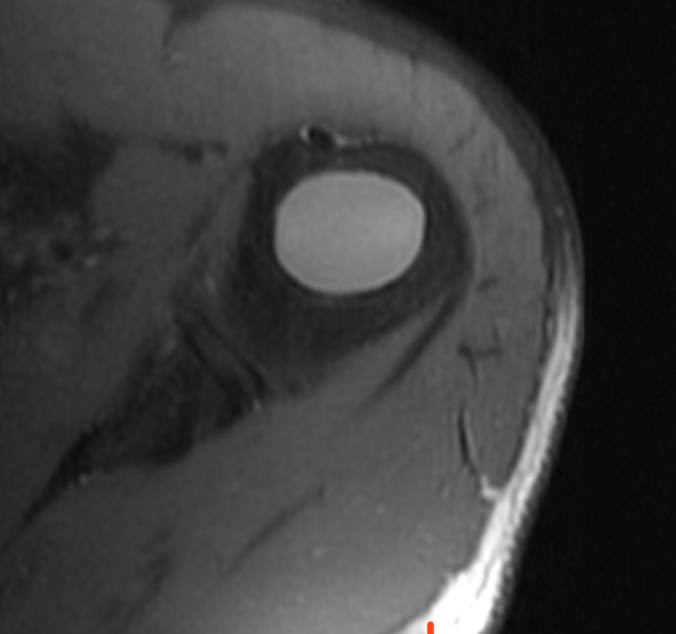

показательный случай острого (хорошо, свежего!) разрыва сухожилия длинной головки бицепса плеча, с приличным диастазом. стрелками указаны края дистального и проксимального фрагментов сухожилия. На последнем снимке - пустая межбугорковая борозда